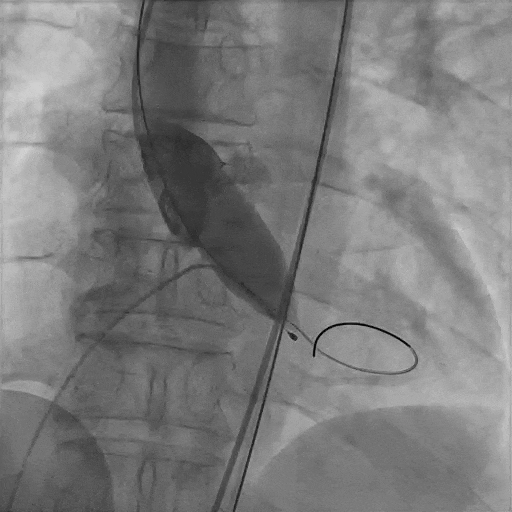

瓣膜初始定位

瓣膜释放至工作体位